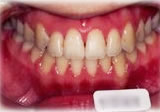

開咬症例

初診時年齢○○歳。前歯部での咬合不全を主訴に来院。

骨格性開咬と診断し、外科的処置を併用して治療。

矯正治療は上下顎歯列を拡大しスペースを作成、非抜歯にて行った。

治療前 治療後

正面 正面 正面